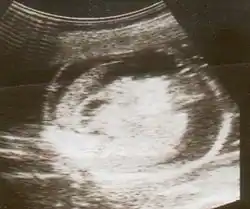

An ultrasound showing a fetus with hydrops fetalis

Hydrops fetalis can be diagnosed and monitored by ultrasound scans.[1] An official diagnosis is made by identifying excess serous fluid in at least one space (ascites, pleural effusion, of pericardial effusion) accompanied by skin edema (greater than 5 mm thick). A diagnosis can also be made by identifying excess serous fluid in two potential spaces without accompanying edema. Prenatal ultrasound scanning enables early recognition of hydrops fetalis and has been enhanced with the introduction of MCA Doppler.[7]